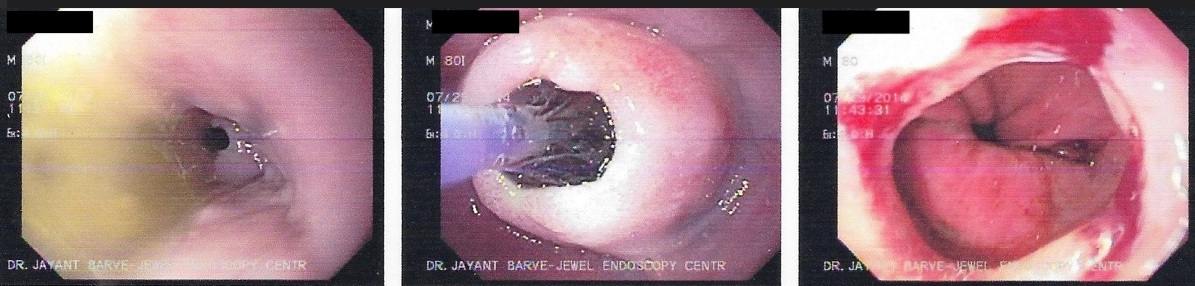

3. Difficulty in swallowing : This is considered as a serious symptom at any age group.

Difficulty in Swallowing

This can be due to severe acidic ulcerations, narrowing of the food passage due to non cancer or

cancerous lesion or pressure on the food pipe from outside.

Cancerous Lesion - Balloon Dilatation as a Palliative Treatment

Strong contractions of the food pipe is known as dysmotility of esophagus and an unusual condition known

as Achalasia Cardia due to powerful contraction of the valve of the esophagus at its lower end which

can cause difficulty in swallowing.

Achalasia Cardia - Balloon Dilatation

Achalasia Cardia - Balloon Dilatation

Achalasia Cardia - Balloon Dilatation

Achalasia Cardia - Balloon Dilatation

4. Diagnosis of Hiatus Hernia